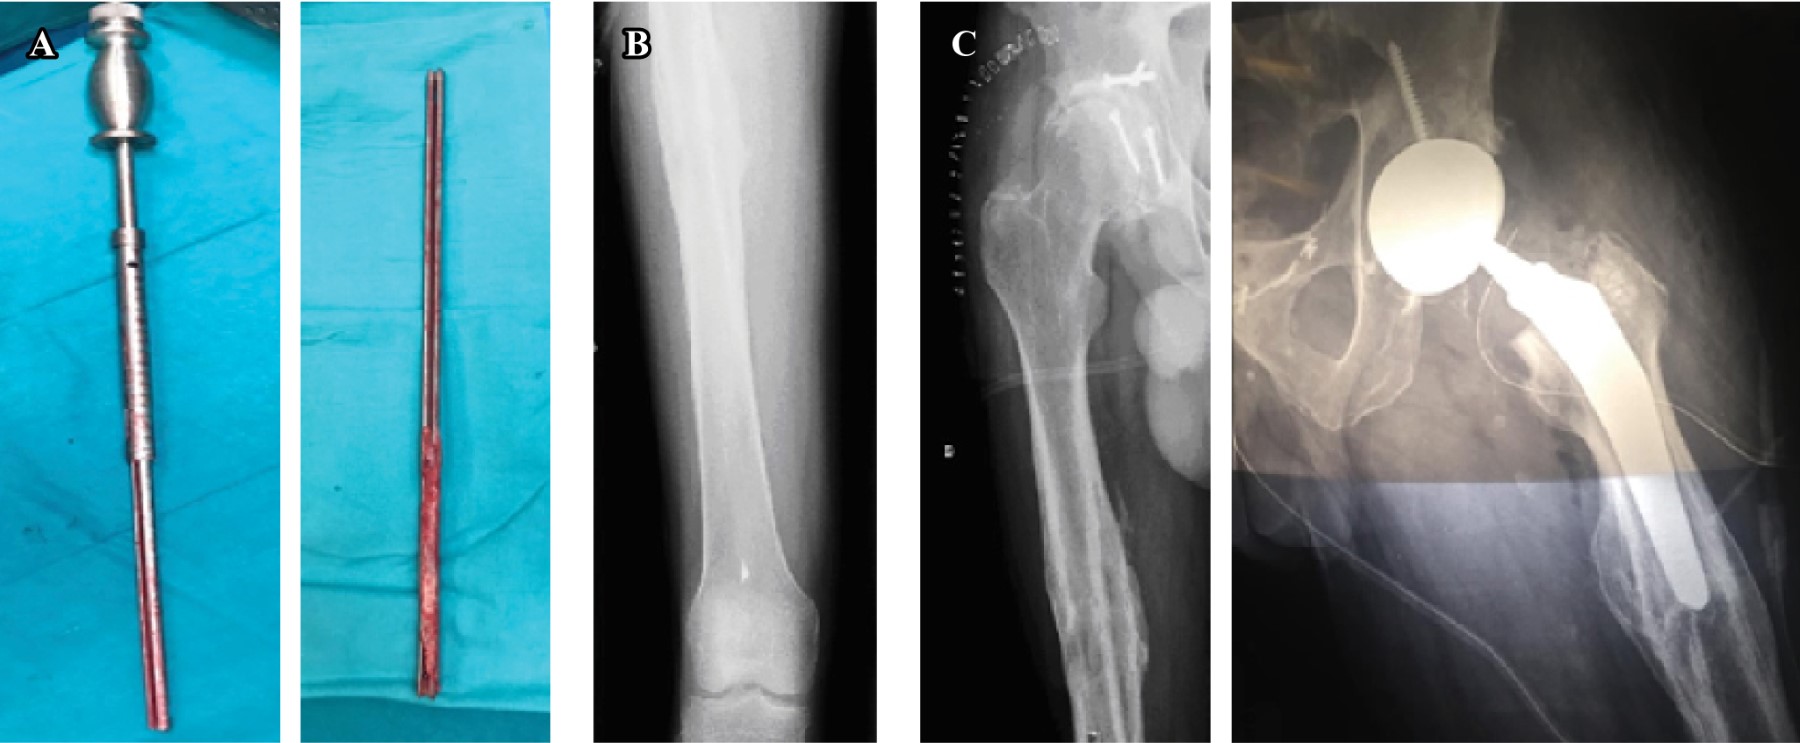

Paciente 1: varón de 47 años con dolor crónico en cadera derecha. Antecedente de fractura de acetábulo y diáfisis femoral tras accidente de tráfico, a los 13 años de edad; sus radiografías preoperatorias se revelan con consolidación de las fracturas y coxartrosis derecha, allí se usó un clavo IM tipo Küntscher sin tornillos de bloqueo (Figura 1A), ya se había intentado extraer seis meses antes sin éxito.

Paciente 2: varón de 48 años con dolor crónico en cadera izquierda. Antecedente de fractura diafisaria de fémur intervenida a los 21 años de edad. Los rayos X confirman la consolidación de la fractura y con clavo IM clase Küntscher sin tornillos de bloqueo (Figura 1B).

Paciente 3: varón de 70 años con dolor crónico en cadera izquierda. Fractura diafisaria de fémur en 1965. En las radiografías se observa coxartrosis y consolidación de la fractura con clavo IM tipo Küntscher sin tornillos de bloqueo, con una discrepancia con longitud de 3 cm (Figura 1C).

Después, con control radiológico, se fresó alrededor del elemento con trefinas del sistema de remoción de vástagos femorales de Depuy-Synthes Johnson & Johnson© (Warsaw, IN USA).5 Este sistema dispone de trefinas de distintos diámetros (11-18.5 mm) de unos 20 cm de longitud. Una vez comprobado que la trefina alcanzó el callo de hueso y quedó encajada, se realizó la extracción, con diapasón, de la trefina junto con el clavo (Figura 2). Se retiraron los aguijones en su totalidad sin complicaciones. Los pacientes permanecieron ingresados 48 horas para control de dolor, iniciando deambulación con carga protegida con muletas y profilaxis antitrombótica.

En el tercer caso, primero se accedió a la articulación coxofemoral, por un abordaje posterolateral. Una vez luxada la cadera, se realizó una osteotomía cervical femoral, que facilitó la localización y fresado con trefinas de la periferia de la pieza. Posteriormente se extrajo con alicates. Tras la retirada del perno se implanta, según técnica reglada, una prótesis total de cadera no cementada: Cotilo Trilogy Zimmer©, a presión, con fijación adicional consistente en tornillo de 6.5 mm; vástago de anclaje metafisario modular M/L Taper Kinectiv Zimmer©; par cerámica-cerámica, cabeza de 36 mm. Se rellenó la zona metafisaria anterior y posterior con hueso de cabeza femoral, buscando aumentar la reserva ósea, sin necesidad de otras maniobras añadidas. Permanece ingresado 72 horas tras iniciar deambulación protegida con muletas y profilaxis antitrombótica.